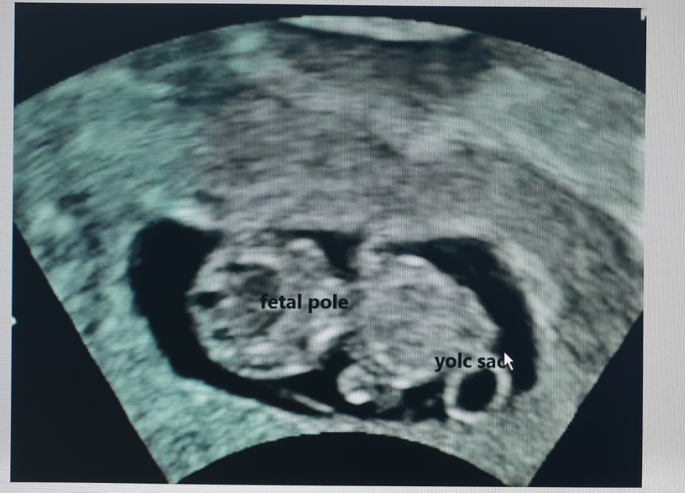

The fetal pole is the first direct imaging manifestation of the fetus and is seen as a thickening on the margin of the yolk sac during early pregnancy . It is often used synonymously with the term "embryo" . The fetal pole is usually identified at . . .

The fetal pole now allows for a crown to rump measurements (CRL) to be taken, so that pregnancy dating can be a bit more accurate . The fetal pole may be seen at a crown-rump length (CRL) of 2-4mm, and the heartbeat may be seen as a regular flutter when the CRL has reached 5mm . If a vaginal ultrasound is done and no fetal pole or cardiac activity is seen, another ultrasound scan should be done in 3-7 days .

Fetal pole . The fetal pole is amass of cells before the embryo is visible . It grows at a rate of about 1 mm a day, starting at the 6th week of gestational age . Thus, a simple way to "date" an early pregnancy is to add the length of the fetal pole (in mm) to 6 weeks . Using this method, a fetal pole measuring 5 mm would have a gestational age of 6 weeks and 5 days .

Given that the fetal pole becomes visible somewhere between 5 1/2 and 6 1/2 weeks of gestational age (typically defined as the fetal age which is determined based on the date of the last normal menstrual period), any small error in dating the pregnancy can throw off an ultrasound interpretation .

Once a fetal pole is present, the crown-rump length should be used to estimate the gestational age as it is the most accurate method of dating the pregnancy . The crown-rump length is defined as the measurement between the top of the head and the bottom of the torso .

Stage Four: Approximately six weeks after a pregnant woman's last period, we can see a small fetal pole , one of the first stages of growth for an embryo, which develops alongside the yolk sac . While these are the expected times to see the developing pregnancy with an ultrasound, not all pregnancies develop along the same timeline .